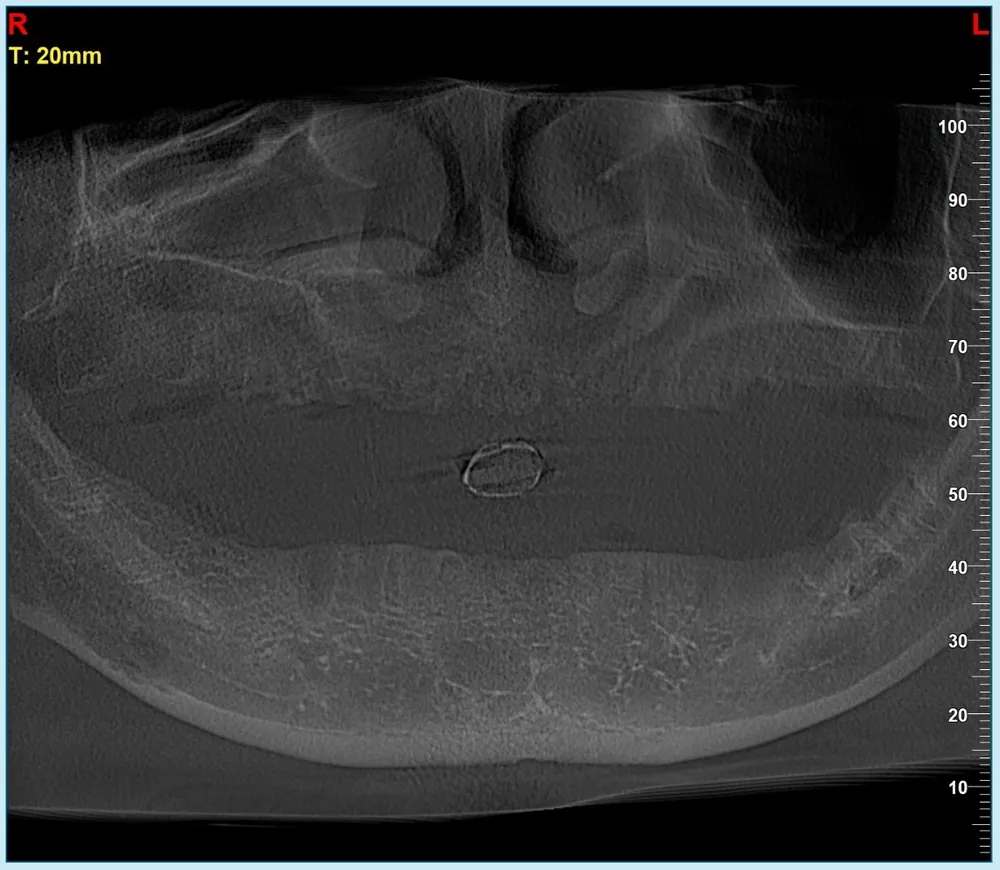

Mất 300 triệu làm răng sứ “dởm”, người đàn ông có ý định tự tử ảnh 1 Hình chụp X-Quang toàn bộ răng bị mất của anh N.P.T.